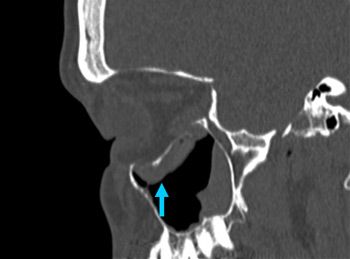

[Figure caption and citation for the preceding image starts]: No evidence of fracture on the left orbit as seen on CT-scan; sagittal reconstructionFrom the personal collection of Dr Alistair Cobb [Citation ends].